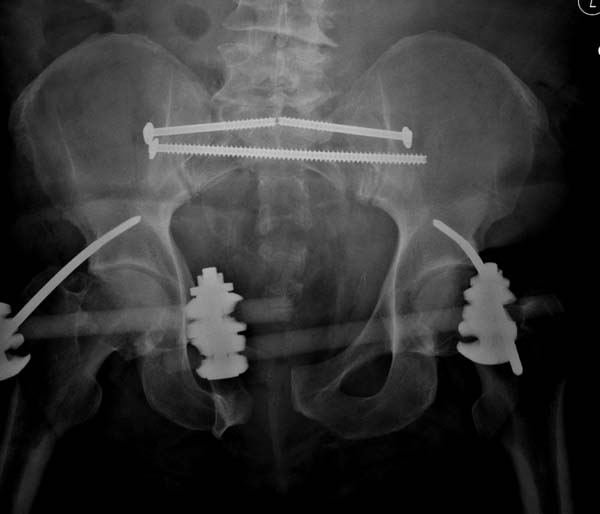

Двухстороннее повреждение крестца и травматическая ампутация бедра, где

неопытной бригадой дежурантов установлен верхний наружный фиксатор для

стабилизации. На третий день ревизия на более стабильный, и

окончательная фиксация. Первые снимки после стабилизации таза, и другие,

где показаны (параллельные) правильная установка на AIIS т.е на месте

прикрепления прямой мышцы бедра. Ампутация закончена костно пластическим

методом.